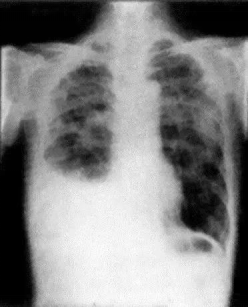

鲁迅去世时给出的说法是死于肺结核,但其实这并不是直接死因。幸好当时还留下来一张胸片。

在1984年,上海市第一结核病防治院邀请23名著名肺科、放射科专家、教授,共同研究这件遗物,并作出了”鲁迅不是直接死于肺结核病,而是死于自发性气胸”的新结论,终于揭开了长达48年的鲁迅死因之谜。

专家认为鲁迅的病情属于中等程度,不是死亡的直接原因,直接原因是左侧肺大疱破裂,使气体进入胸膜引起自发性气胸,压迫肺和心脏死亡。同时认为,这种病在当时并不是不治之症,如果及时治疗,是完全可以治好的,遗憾的是,庸医须藤诊断失误。